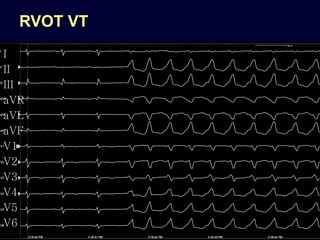

RVOT VT

I

II

III

aVR

aVL

aVF

V1

V2

V3

V4

V5

V6

RVOT VT morphology